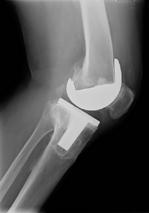

H O F T E - O G K N E P R O T S E R

Vi er stolte over å tilby kne- og hofteproteseoperasjoner E E

Hvorfor henvise til oss?

Rask time uten ventetid Rask time uten ventetid

Erfarne spesialister

Moderne fasiliteter i Bergen